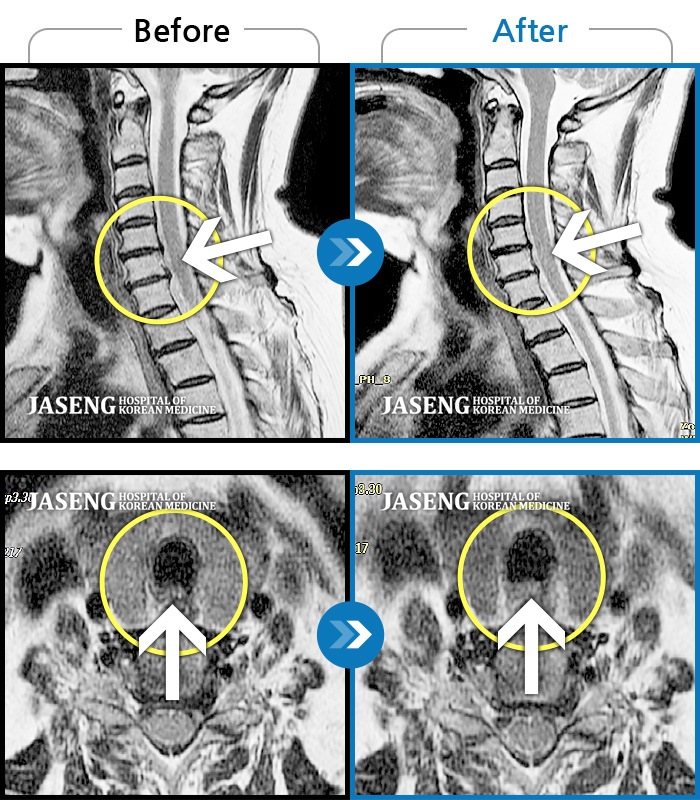

목디스크

도움받은 사례

인천 · 강아현 원장

처음 내원시 목에서 등으로 이어지는 통증 및 우측 팔 저림 증상이 심했고, 약간의 근력저하도 동반되어 일상생활이 어려운 상태였습니다.

촬영시기

2024.04.06 ~ 2024.11.16

2024.11.22